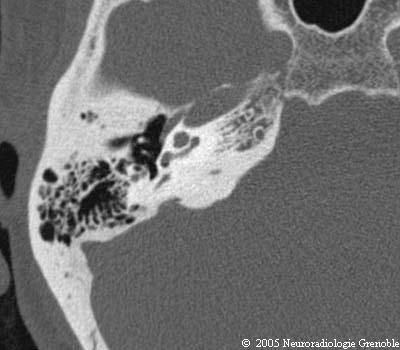

Radioanatomie TDM du rocher normal

Cochlée (tour basal)

Cochlée (2ème tour)

Canal semi-circulaire postérieur

Fenêtre cochléaire (ronde)

Aqueduc de la cochlée

Aqueduc du vestibule

Marteau (manche)

Enclume (longue apophyse)

Membrane tympanique

Canal du muscle de l'étrier

Canal du facial (3ème portion)

Canal du muscle du marteau

Cellule épitympanique antérieure

Mésotympan

Sinus tympani

Méat acoustique externe